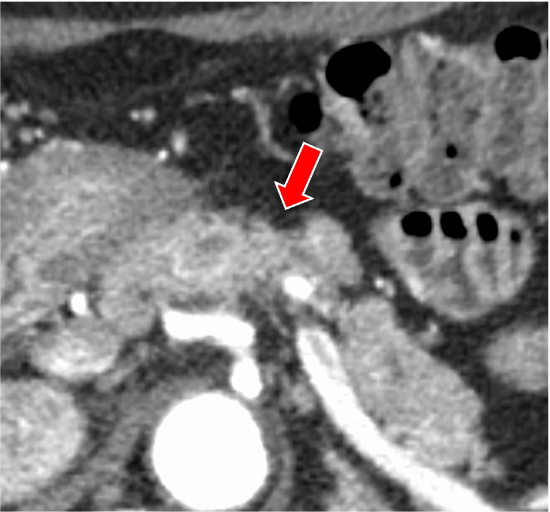

膵ダイナミックCTの膵実質相120kVp画像(図1)で膵体部に限局性萎縮(赤矢印)を認めるが、膵癌を疑わせるような低吸収域は同定できない。遅延相120kVp画像(図2)では萎縮部近傍にごく淡い高吸収域(黄矢印)を認め、線維性間質に富む膵癌の可能性が示唆される。Dual-energy CTの仮想単色低エネルギー画像(図3)およびヨード密度画像(図4)では遅延濃染域が明瞭化しており、膵癌の診断確信度が向上する。膵体尾部切除術が施行され、高分化型浸潤性膵管癌(腫瘍径6mm、pT1a)と最終診断された。術後、補助化学療法が行われ、現在まで無再発で経過している。

膵癌は最も予後不良な悪性腫瘍のひとつであり、早期診断が極めて重要である。CTは膵癌診断の主軸を担う画像診断モダリティで、病変の検出や病期診断などに必要不可欠な役割を果たしている。膵癌は線維性間質に富む腫瘍であり、造影CTで早期相から遅延相にかけて漸増性に増強される。これに対して正常膵は膵実質相で造影効果が最大化し、その後漸減する。このため、典型的な膵癌は膵実質相において低吸収を示し、このタイミングで最も明瞭に描出される。しかし、サイズの小さな早期膵癌は線維性間質や壊死が少なく、膵実質相で等吸収を示す傾向がある。その場合、限局性の膵萎縮や淡い遅延性増強効果が病変検出の鍵となるが、これらの変化はわずかなことが多く、従来のsingle-energy CTでは、早期膵癌を高い確信度で診断するのが困難である。

CT技術や撮像プロトコル設定について